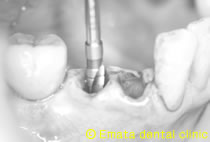

抜歯と同時にインプラント埋入、無切開で行く予定で、抜歯の部位とドリルを合わせています。 |